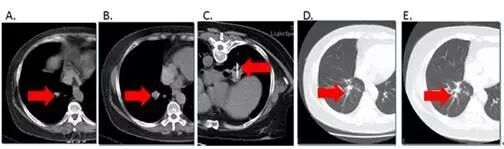

用于晚期非小细胞肺癌患者中酪氨酸激酶抑制剂(TKI)包括如凯美纳、易瑞沙或特罗凯等局部耐药后的治疗。如TKI治疗已经成为晚期非小细胞肺癌中表皮生长因子受体(EGFR)敏感突变患者的一线治疗选择。邵逸夫医院肿瘤研究中心采用RFA技术用于姑息性治疗非小细胞肺癌并克服TKI耐药的可选择治疗方法之一(如图2)。

图4:1 例59岁女性晚期非小细胞肺癌患者(EGFR突变)伴肺内转移,口服TKI药物治疗后15月,右下肺肿瘤(图B)如箭头所示较前(图A)明显增大,疾病进展;经CT引导下右下肺肿瘤RFA治疗(图C),后随访3个月(图D)、6个月(图E)均示控制良好。